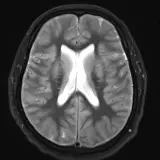

Neuro MRI